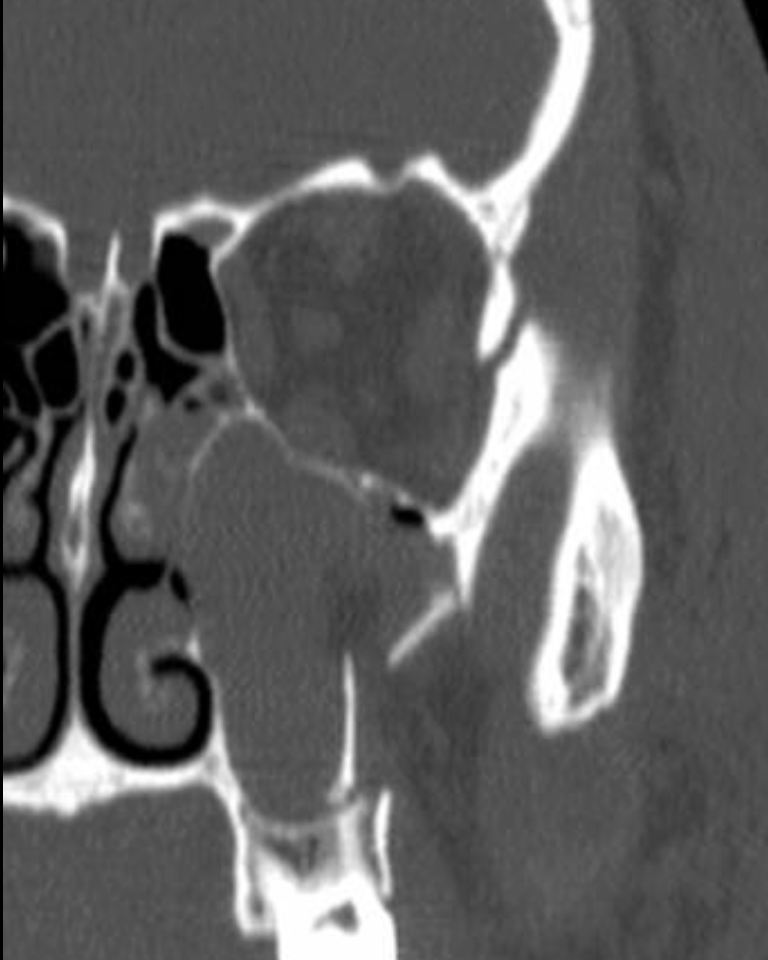

47M presents with multiple facial injuries following high impact car accident where he slammed the side of his chin/face into steering wheel. Endorses malocclusion. CT max face shows medial displacement of condyle.

Where does he most likely have fractures? In what order should they be repaired and how?

R condylar neck fx and L mandibular body or parasymphysis fx

First, you place pt in pre-morbid occlusion with arch bars and MMF. Then, you repair fx's within dental arch, moving anterior to posterior to guarantee proper occlusion. At the end, you reduce edentulous fractures (ie. condyle)

Can use 1 monocortical mini plate (2.0mm) per fracture making sure to have 3 holes on each side.

**studies no longer support needing rigid fixation of one of the fractures (with 2 mini plates, locking plate or 2.0 recon plate) - https://pubmed.ncbi.nlm.nih.gov/37772893/

Then you can treat the condylar neck fracture with MMF for 2 weeks or fixate it with 1-2x 2.0mm miniplates depending on height of fx.